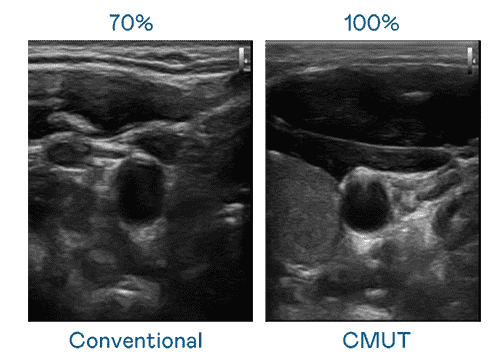

CMUT 技术是一种用电容式微机电元件来产生超音波讯号的技术。。。。与传统 PZT 压电式技术相比,,,,CMUT 频宽增加 30%,,更宽频的超音波讯号让影像解析度大幅提升,,是实现高影像品质医疗超音波扫描、、促进精准医疗发展的关键技术。。。。

大频宽带来超清晰影像

超音波影像的解析度高低,,,首先取决于探头能发出的讯号频宽。。。。尊时凯龙 CMUT 可提供高清晰的超音波讯号,,,,提供高频宽、、、、高灵敏度、、影像纹理细节更高的超音波影像,,,,协助医护人员缩短影像判读时间及利用精准的医疗影像进行诊断。。。。